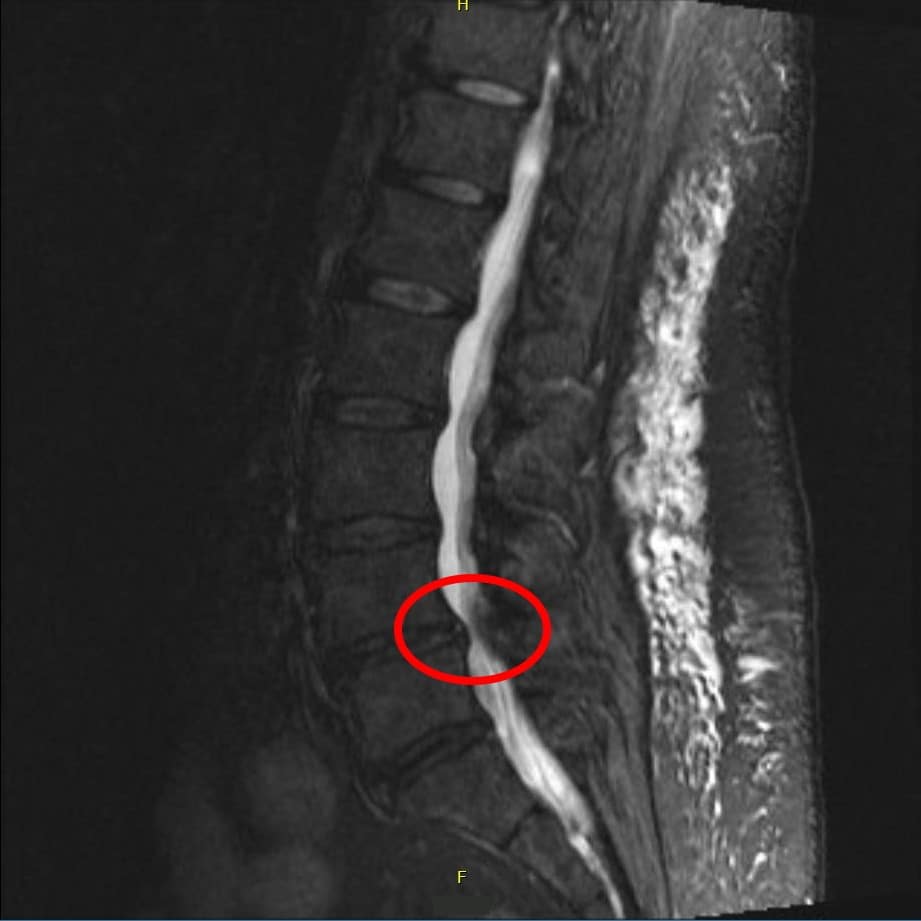

The main tool for making the diagnosis is the history. Imaging can supplement the history and of course helps with planning treatment. MRI is the test to order. An alternative is CT myelography. Narrowing of the spinal canal suggests spinal stenosis. The problem is that ~20% of adults over 60 will have narrowing without symptoms.